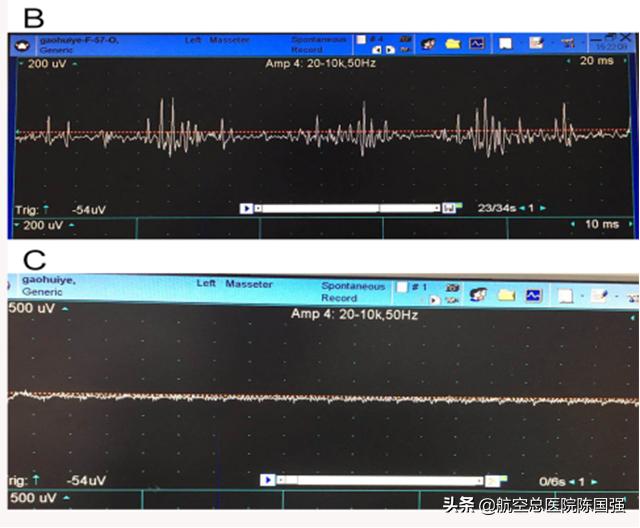

B为术前肌电无规律的高频率及高波幅的群放电;C术后肌电图:异常肌电消失